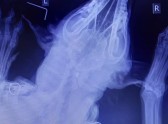

По словам Юлии, пострадавший пес был доставлен в ветклинику на рентген. Снимки, которые там сделали, показали, что пуля, разорвавшись на осколки, застряла в мягких тканях.

- У Джерри, кроме болевого синдрома, болезненности в районе шейного отдела, воспаления в районе отверстия от пули, шока и стресса, обнаружено нарушение чувствительности правой части морды и, как видно по фотографиям, так называемое "западение глаза": по всей вероятности, задет нерв, - так же рассказывает девушка.